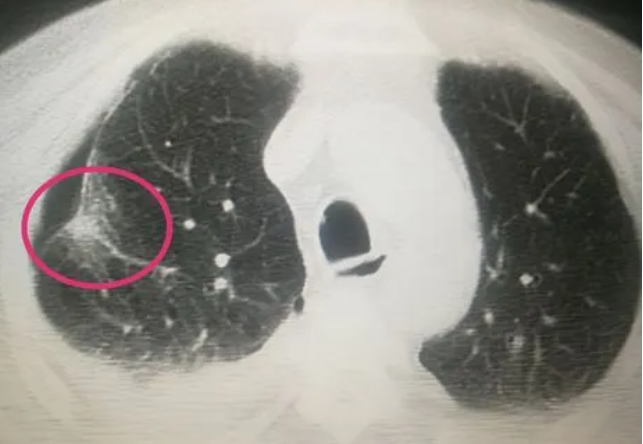

肺部结节是指肺内的异常肿块或者结节,大多是通过肺部影像学检查如X光或者CT扫描被发现。虽然肺结节性质通常为良性,但也不能完全排除是肺癌早期表现的可能性,仍需要密切关注并接受医生的建议和治疗。而在饮食方面,很多人得知自己患有肺部结节后都会担心是否需要忌口以及哪些食物需要少吃。